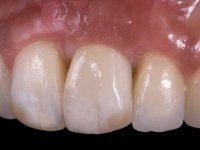

A paciente de sexo feminino de 28 anos de idade perdeu por traumatismo o incisivo central superior esquerdo. Preocupada com o seu sorriso, a paciente apareceu no consultório querendo alinhar os dentes antero-superiores para obter uma aparência mais natural. Sendo fumadora a paciente não apresentava problemas médicos dignos de registo.

A paciente apresenta um desvio da linha média superior de 6 mm para a esquerda. Resultado da ausência do incisivo central superior esquerdo, os dentes adjacentes inclinaram mesialmente para esta zona, limitando o espaço disponível para a reabilitação prostodontica. Existe uma significativa desarmonia dentária negativa no arco maxilar como resultado da ausência do 21, ausência do primeiro pre-molar com um espaço residual, significativa redução coronária do segundo pre-molar direito, migração dos dentes posteriores para os espaços não preenchidos e uma mesialização molar superior esquerda e direita com uma relação molar em Classe II. Ambos os caninos esquerdo e direito mostram uma relação Classe II na posição de inter-cuspidação máxima. A paciente apresenta uma linha de sorriso média, um biótipo gengival médio grosso, apresenta uma correcta higiene oral sem doença periodontal. Não apresenta hábitos para –funcionais. O exame radiográfico mostra uma significativa inclinação dos eixos dos dentes 11 e 22 com espaço entre a porção apical das raízes. A análise cefalométrica foi feita com o intuito de explorar a hipótese de conseguir arranjar espaço para a colocação de um implante e de uma coroa no local do dente 21. Finalmente a morfologia do osso residual presente na região anterior da maxila foi avaliado com uma TAC, revelando uma perda das dimensões da parede óssea vestibular.

A confecção de um coto de óxido de zircónio com uma coroa de cerâmica vítrea prensada de dissilicato de lítio mimetizou perfeitamente os dentes vizinhos.